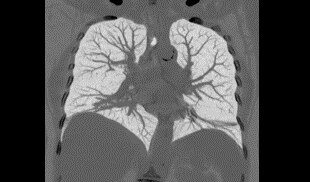

Vücut Görüntü Galerisi